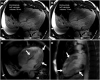

Various clinical presentations of the 2019 coronavirus disease (COVID-19) have been described, including post-infectious acute and fulminant myocarditis. Here, we describe the case of a young patient admitted for COVID-19-associated post-infectious fulminant myocarditis. Despite optimal pharmacologic management, haemodynamic status worsened requiring support by veno-arterial extracorporeal membrane oxygenation. Emergent heart transplantation was required at Day 11 given the absence of cardiac function improvement. The diagnosis of post-infectious COVID-19-associated myocarditis was made from both pathologic examination of the explanted heart and positive SARS-CoV-2 serology.